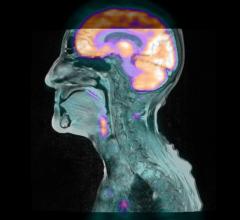

Using a sophisticated magnetic resonance imaging (MRI) technique, researchers have found abnormalities in the brain’s white matter tracts in patients with insomnia.